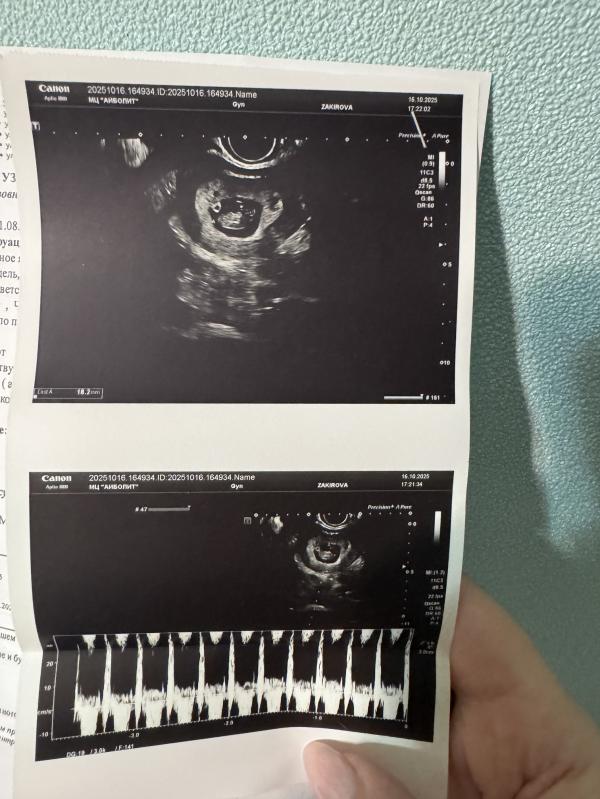

Когда вставать на учет в консультацию после УЗИ с сердцебиением

Вчера была на узи, услышала наконец-то сердечко малыша

Теперь могу вставать же на учет в консультацию?